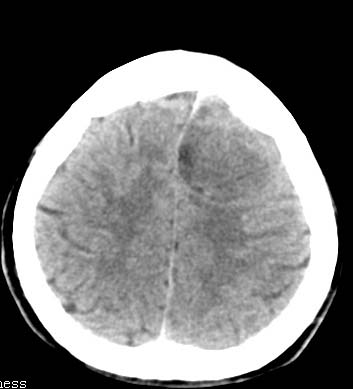

以下是引用卜一在2007-8-29 6:48:00的发言:[br]左侧额叶不均匀密度影,占位效应明显,界限不清。支持:占位性病变,建议增强!

以下是引用clj20在2007-8-29 9:47:00的发言:[br]蛛网膜下腔出血,左侧额叶不均匀密度影,占位效应明显,界限不清。支持:占位性病变,建议增强!

以下是引用xulianj在2007-8-29 20:15:00的发言:[br]蛛网膜下腔出血,左侧额叶不均匀密度影,占位效应明显,界限不清。支持:占位性病变,建议增强!

以下是引用jiangjing在2007-8-29 14:33:00的发言:[br]左侧额叶不均匀密度影[低密度为主,边缘见等密度环环绕]占位效应明显,界限不清。支持:占位性病变,建议增强! [br][br]